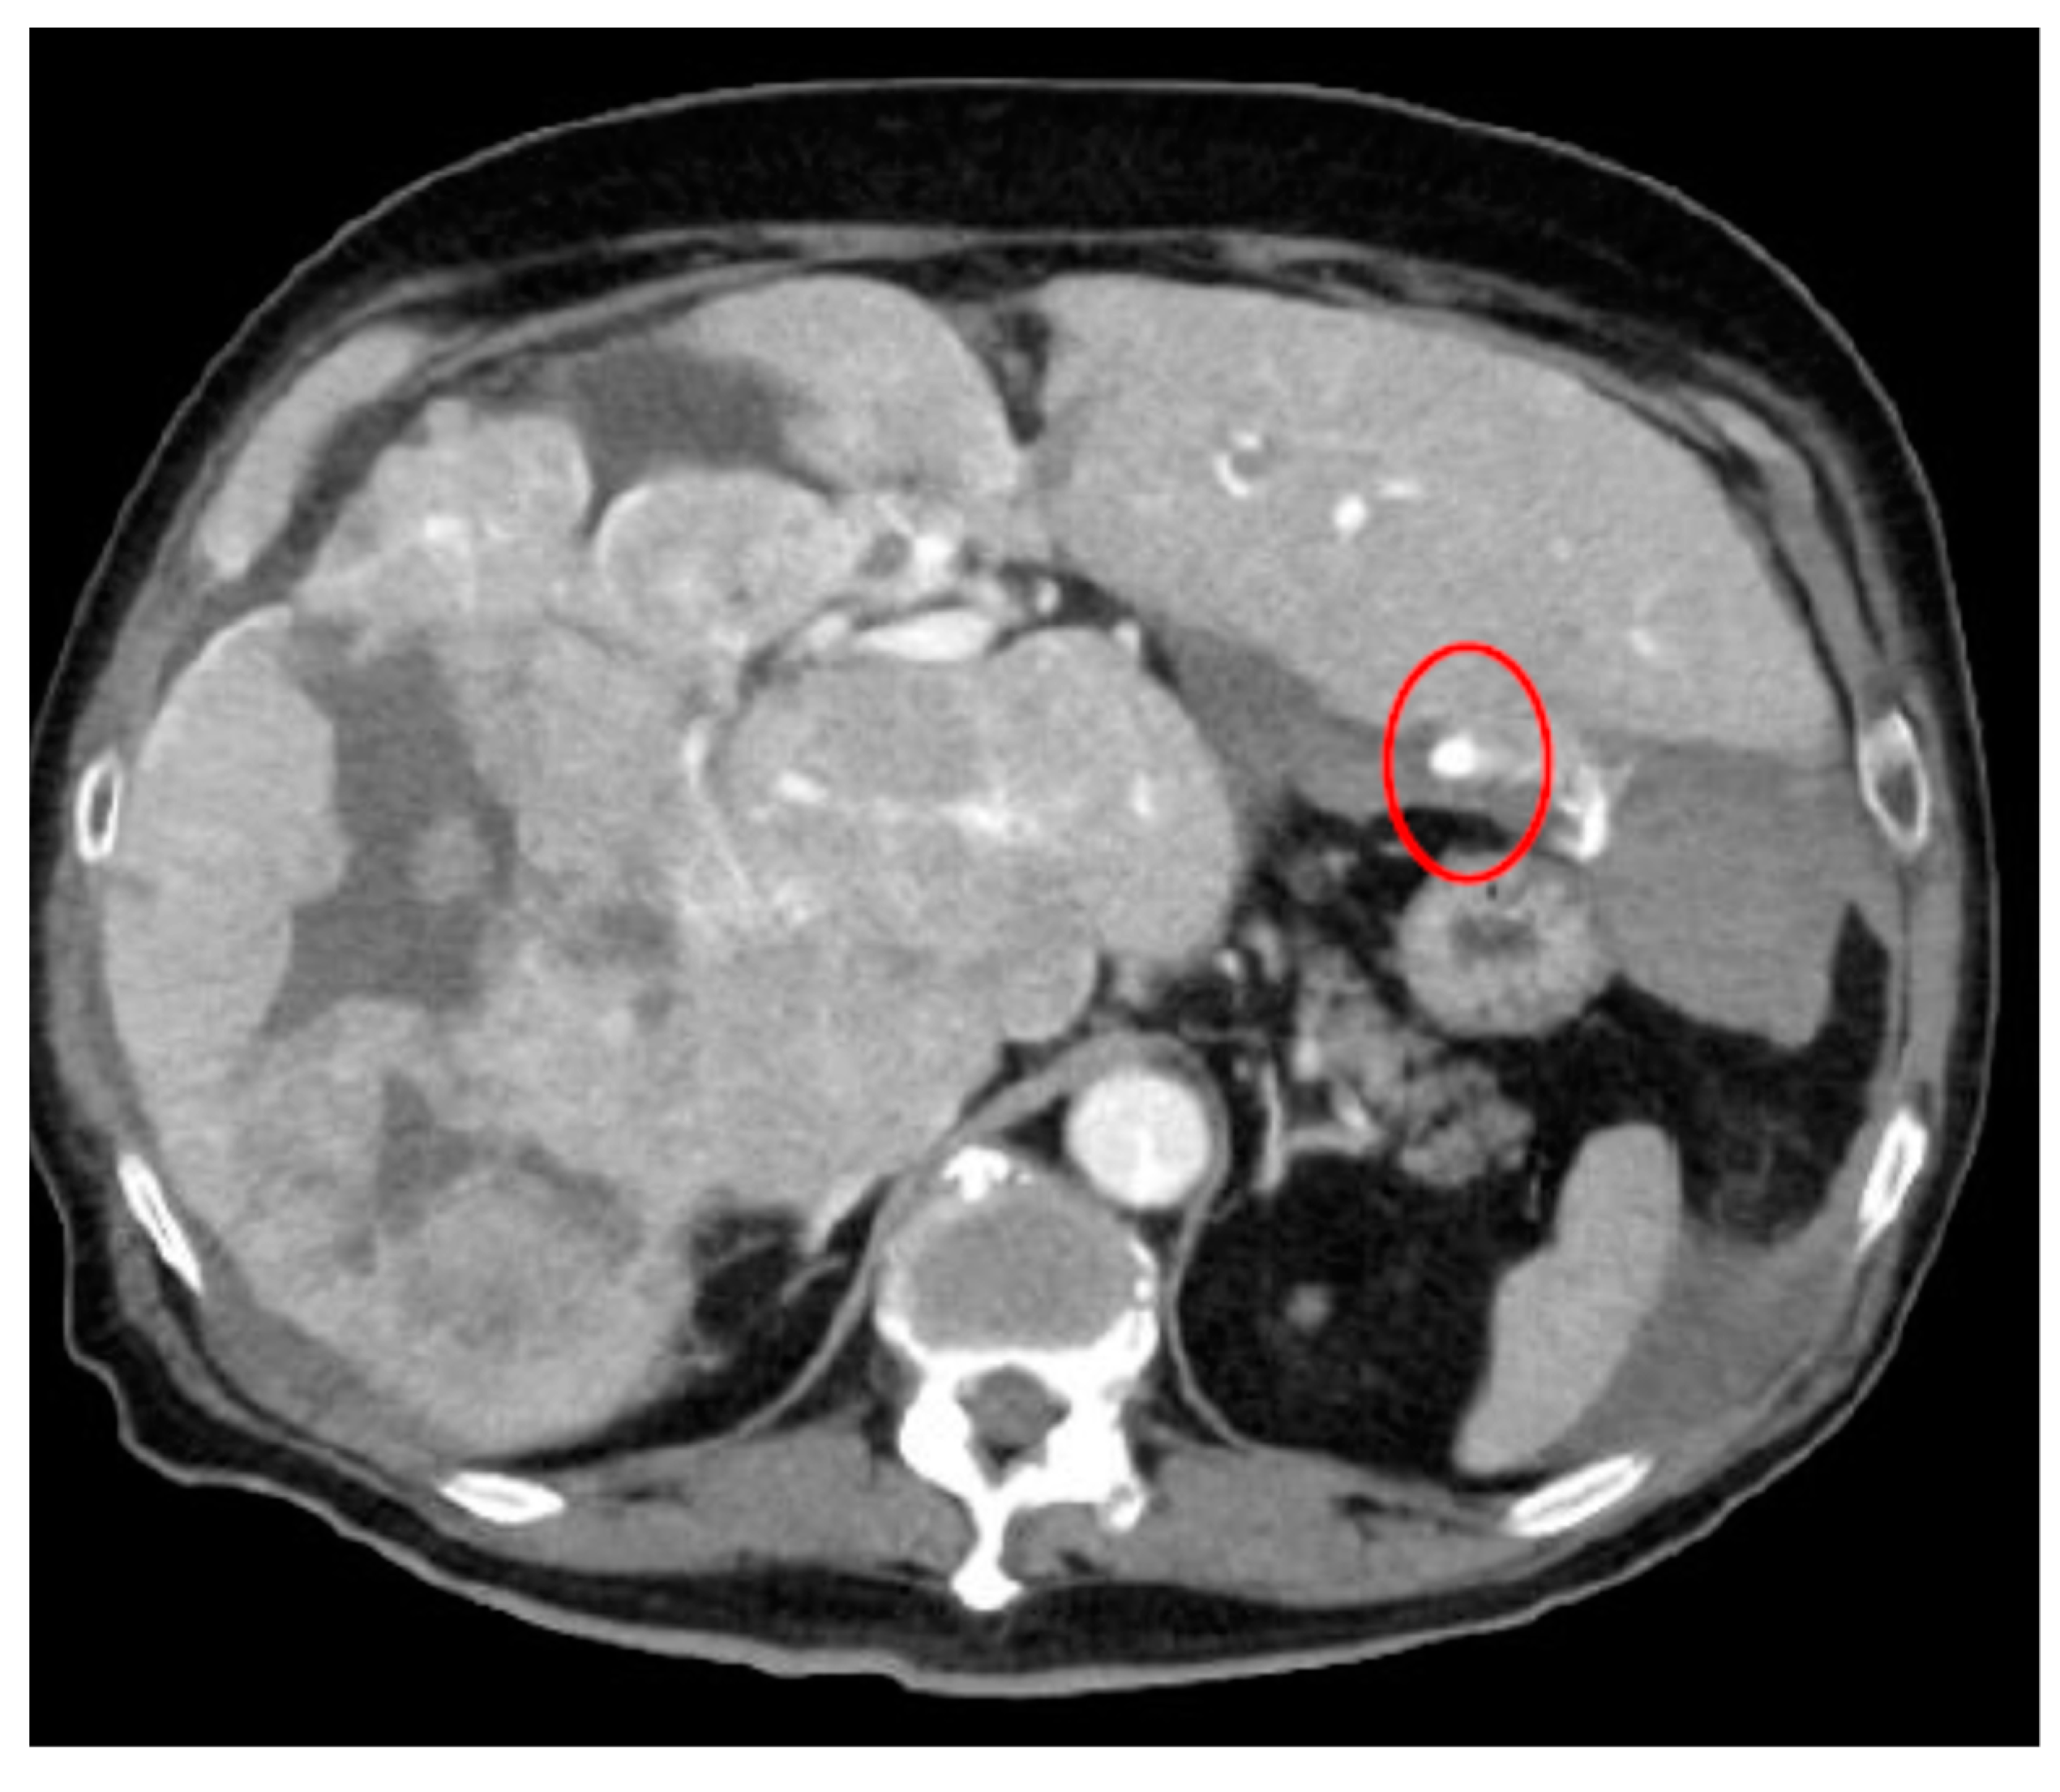

- AI for Image Analysis: AI-based image analysis algorithms can enhance the detection and diagnosis of extravasation events in imaging studies, such as ultrasound, MRI, and CT. These algorithms can automatically identify subtle signs of extravasation, assist healthcare providers in interpreting the imaging findings, and facilitate a timely intervention. This suggestion is subsequently extended as a separate discussion.

- Albano, D.; Benenati, M.; Bruno, A.; Bruno, F.; Calandri, M.; Caruso, D.; Cozzi, D.; De Robertis, R.; Gentili, F.; Grazzini, I.; et al. Imaging side effects and complications of chemotherapy and radiation therapy: A pictorial review from head to toe. Insights Imaging 2021, 12, 76. [Google Scholar] [CrossRef] [PubMed]